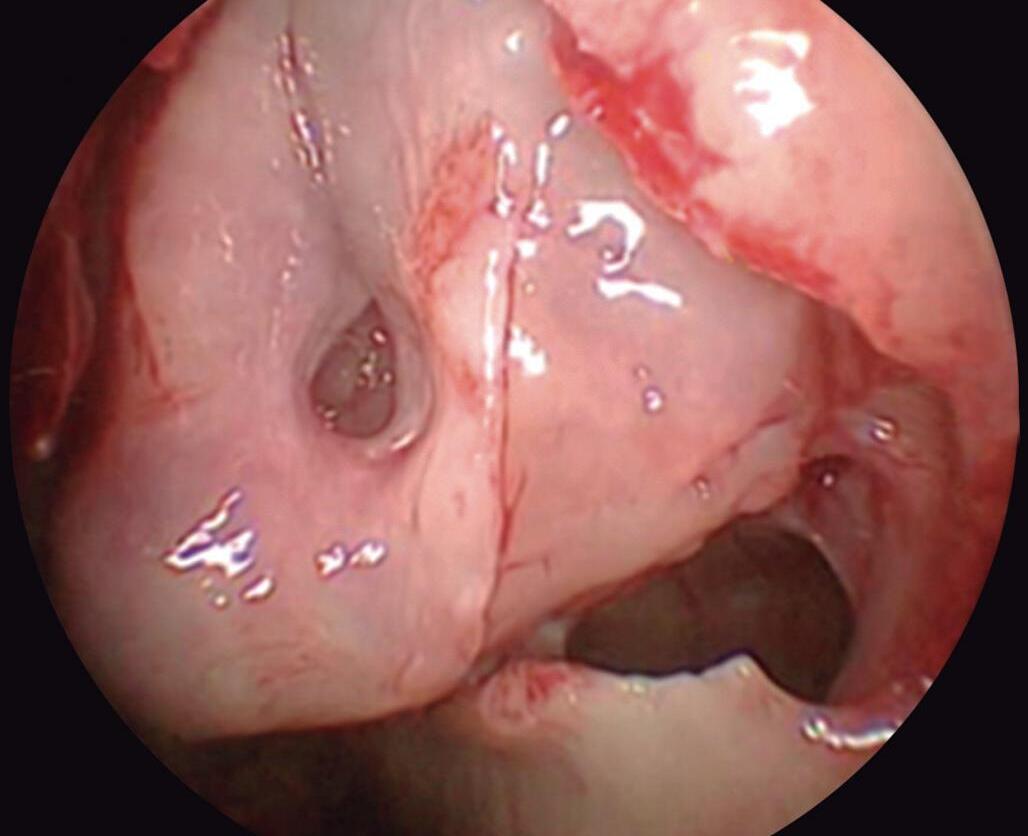

No interior do meato médio, o processo uncinado (PU), situado anteriormente (barreira de fluxo inspiratório); a face meatal da concha média (internamente) e sua lamela basal (posterossuperiormente), formam uma grande câmara aerodinâmica. Esta, por sua vez, é dividida estrategicamente pela bulha etmoidal (BE) em vários recessos laterais que permitem o funcionamento e a drenagem dos seios maxilar e frontal além de eventuais células etmoidais vizinhas. Nenhuma cavidade do seio etmoidal é fechada.

O processo uncinado e a bulha etmoidal limitam entre si um espaço vazio em forma de meia-lua (hiato semilunar) que se continua numa profunda depressão (infundíbulo), recebendo superiormente a drenagem do seio frontal e inferiormente do seio maxilar. A posição exata destes orifícios é variável dentro deste espaço anatômico.

O meato médio, por servir fisiologicamente aos seios frontal e maxilar, é o mais complexo e o comportamento anatômico do processo uncinado e da bulha etmoidal é arquitetonicamente combinado para exercer função predeterminada. Ambas as estruturas, embora com formatos distintos, ancoram-se ou estão acopladas à parede medial da órbita.

1-13. Montagem em aspecto endoscópico e peça anatômica (Bagatella) demonstrando a relação do processo uncinado e bulha etmoidal com a parede medial da órbita: (1) porção meatal da concha média; (2) processo uncinado; (3) bulha etmoidal; (4) parede medial da órbita.